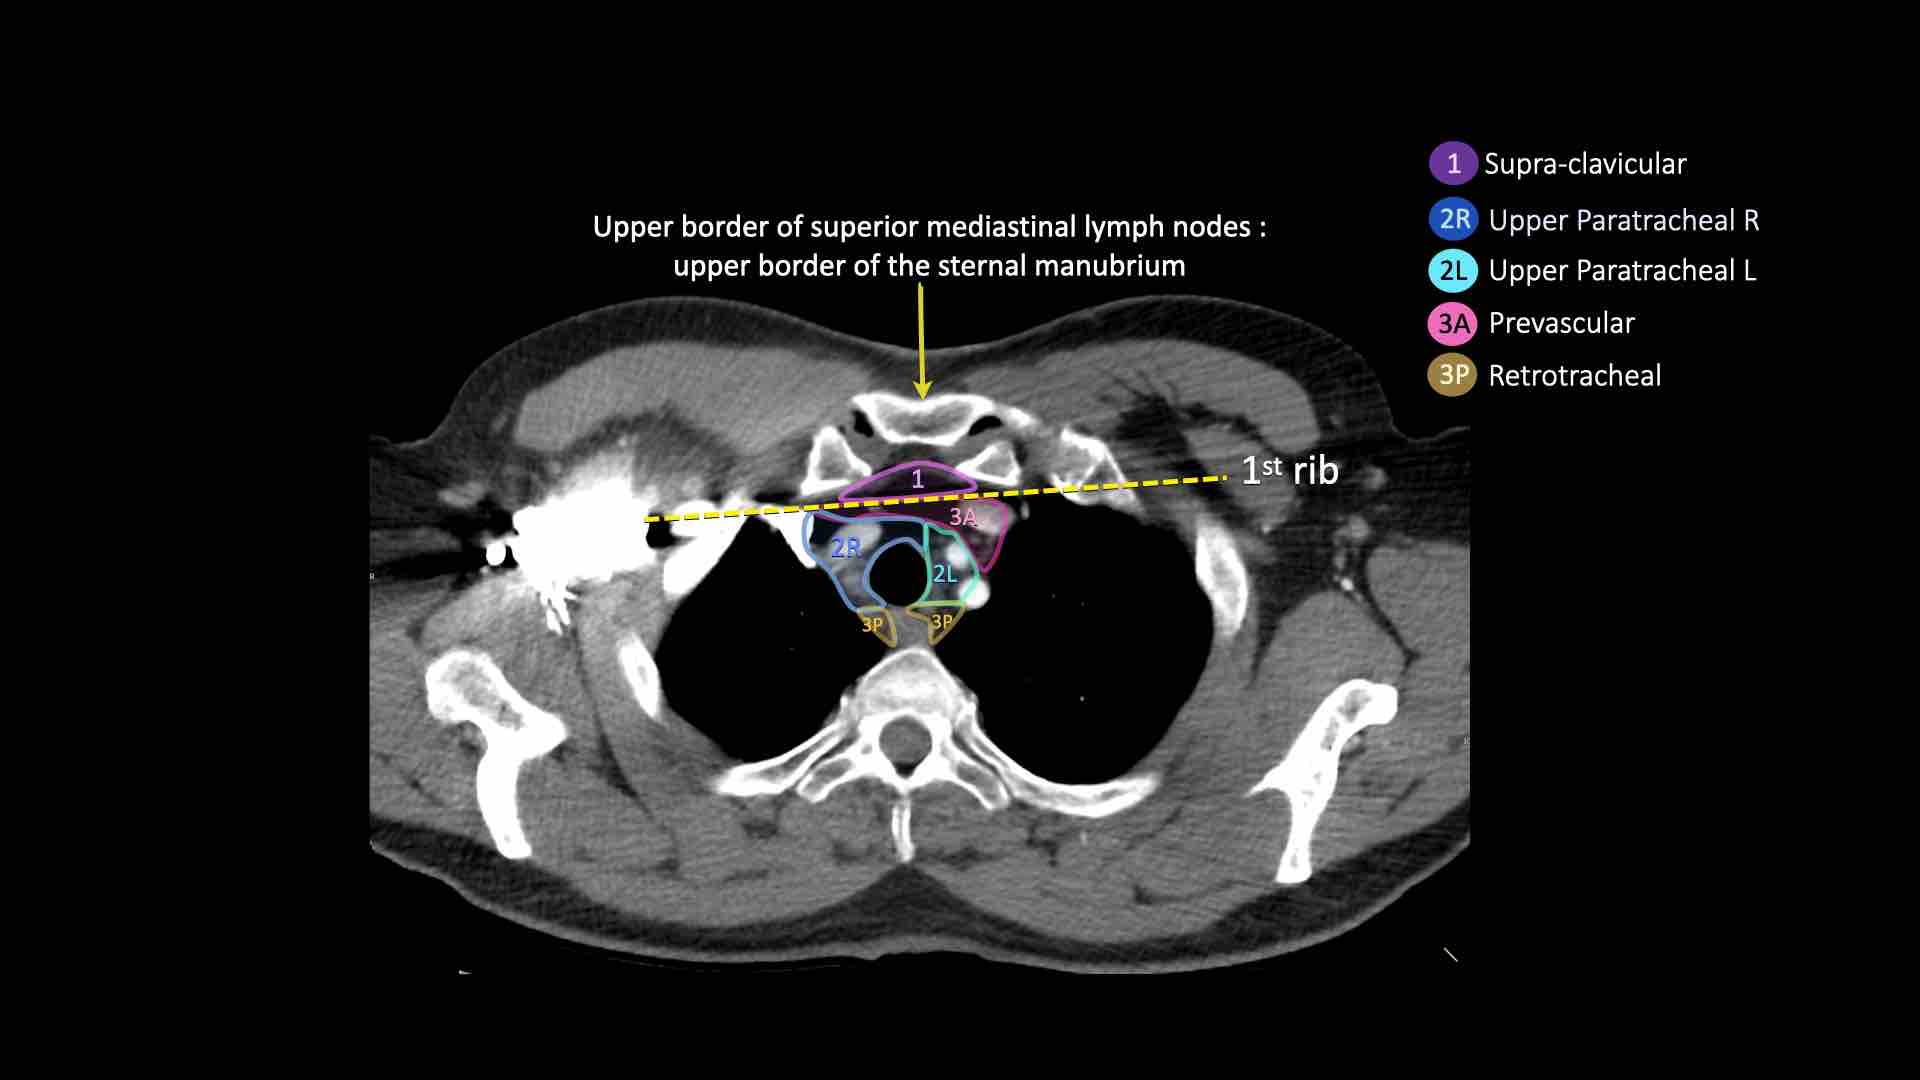

2R. Hạch cạnh khí quản trên bên phải

Hạch nhóm 2R trải dài đến bờ bên trái của khí quản.

Ranh giới trên: bờ trên cán ức.

Ranh giới dưới: giao điểm của bờ dưới tĩnh mạch vô danh (tĩnh mạch tay đầu trái) với khí quản.

2L. Hạch cạnh khí quản trên bên trái

Ranh giới dưới: bờ trên quai động mạch chủ.

3. Hạch trước mạch máu và trước cột sống

Hạch nhóm 3 không nằm kề khí quản như hạch nhóm 2.

Chúng có thể là:

3A nằm phía trước các mạch máu, hoặc

3B nằm phía sau thực quản, vốn nằm ở vị trí trước cột sống.

- Hạch bạch huyết khuyết ức có thể quan sát thấy ở mức này và phía trên mức này

- Cạnh khí quản trên: phía dưới xương đòn, bên phải nằm trên giao điểm của bờ dưới tĩnh mạch vô danh (tĩnh mạch tay đầu trái) với khí quản, bên trái nằm trên cung động mạch chủ

- Trước mạch máu và Sau khí quản: nằm trước các mạch máu (3A) hoặc trước cột sống (3P)